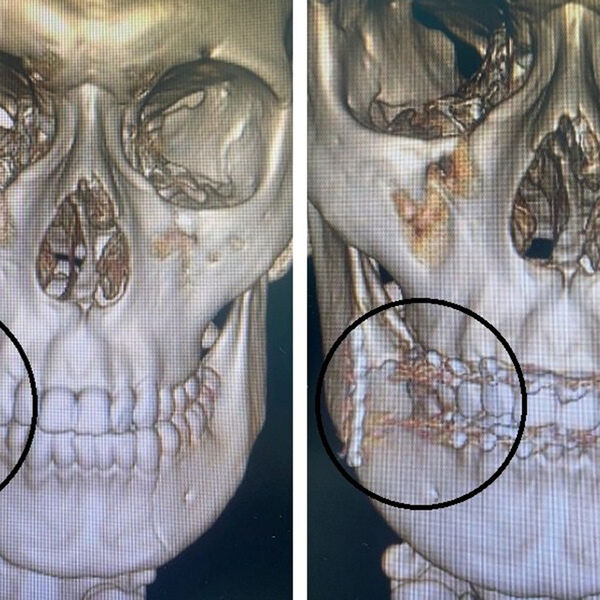

«После осмотра и диагностики был поставлен диагноз — открытый двусторонний перелом нижней челюсти. Мальчика госпитализировали в отделение оториноларингологии и челюстно-лицевой хирургии для проведения хирургического лечения», — рассказал челюстно-лицевой хирург больницы Владислав Слепов.

Доктор отметил, что сначала подростку наложили шины на верхнюю и нижнюю челюсти, а затем во время операции скрепили нижнюю челюсть титановой пластиной. Юноше предстоит долгое время питаться через трубочку — как пояснил медик, для полного срастания отломков необходимо полностью обездвижить челюсть.